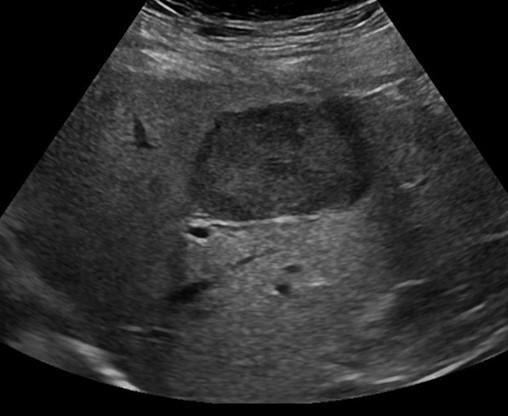

Pyogenic Abscess